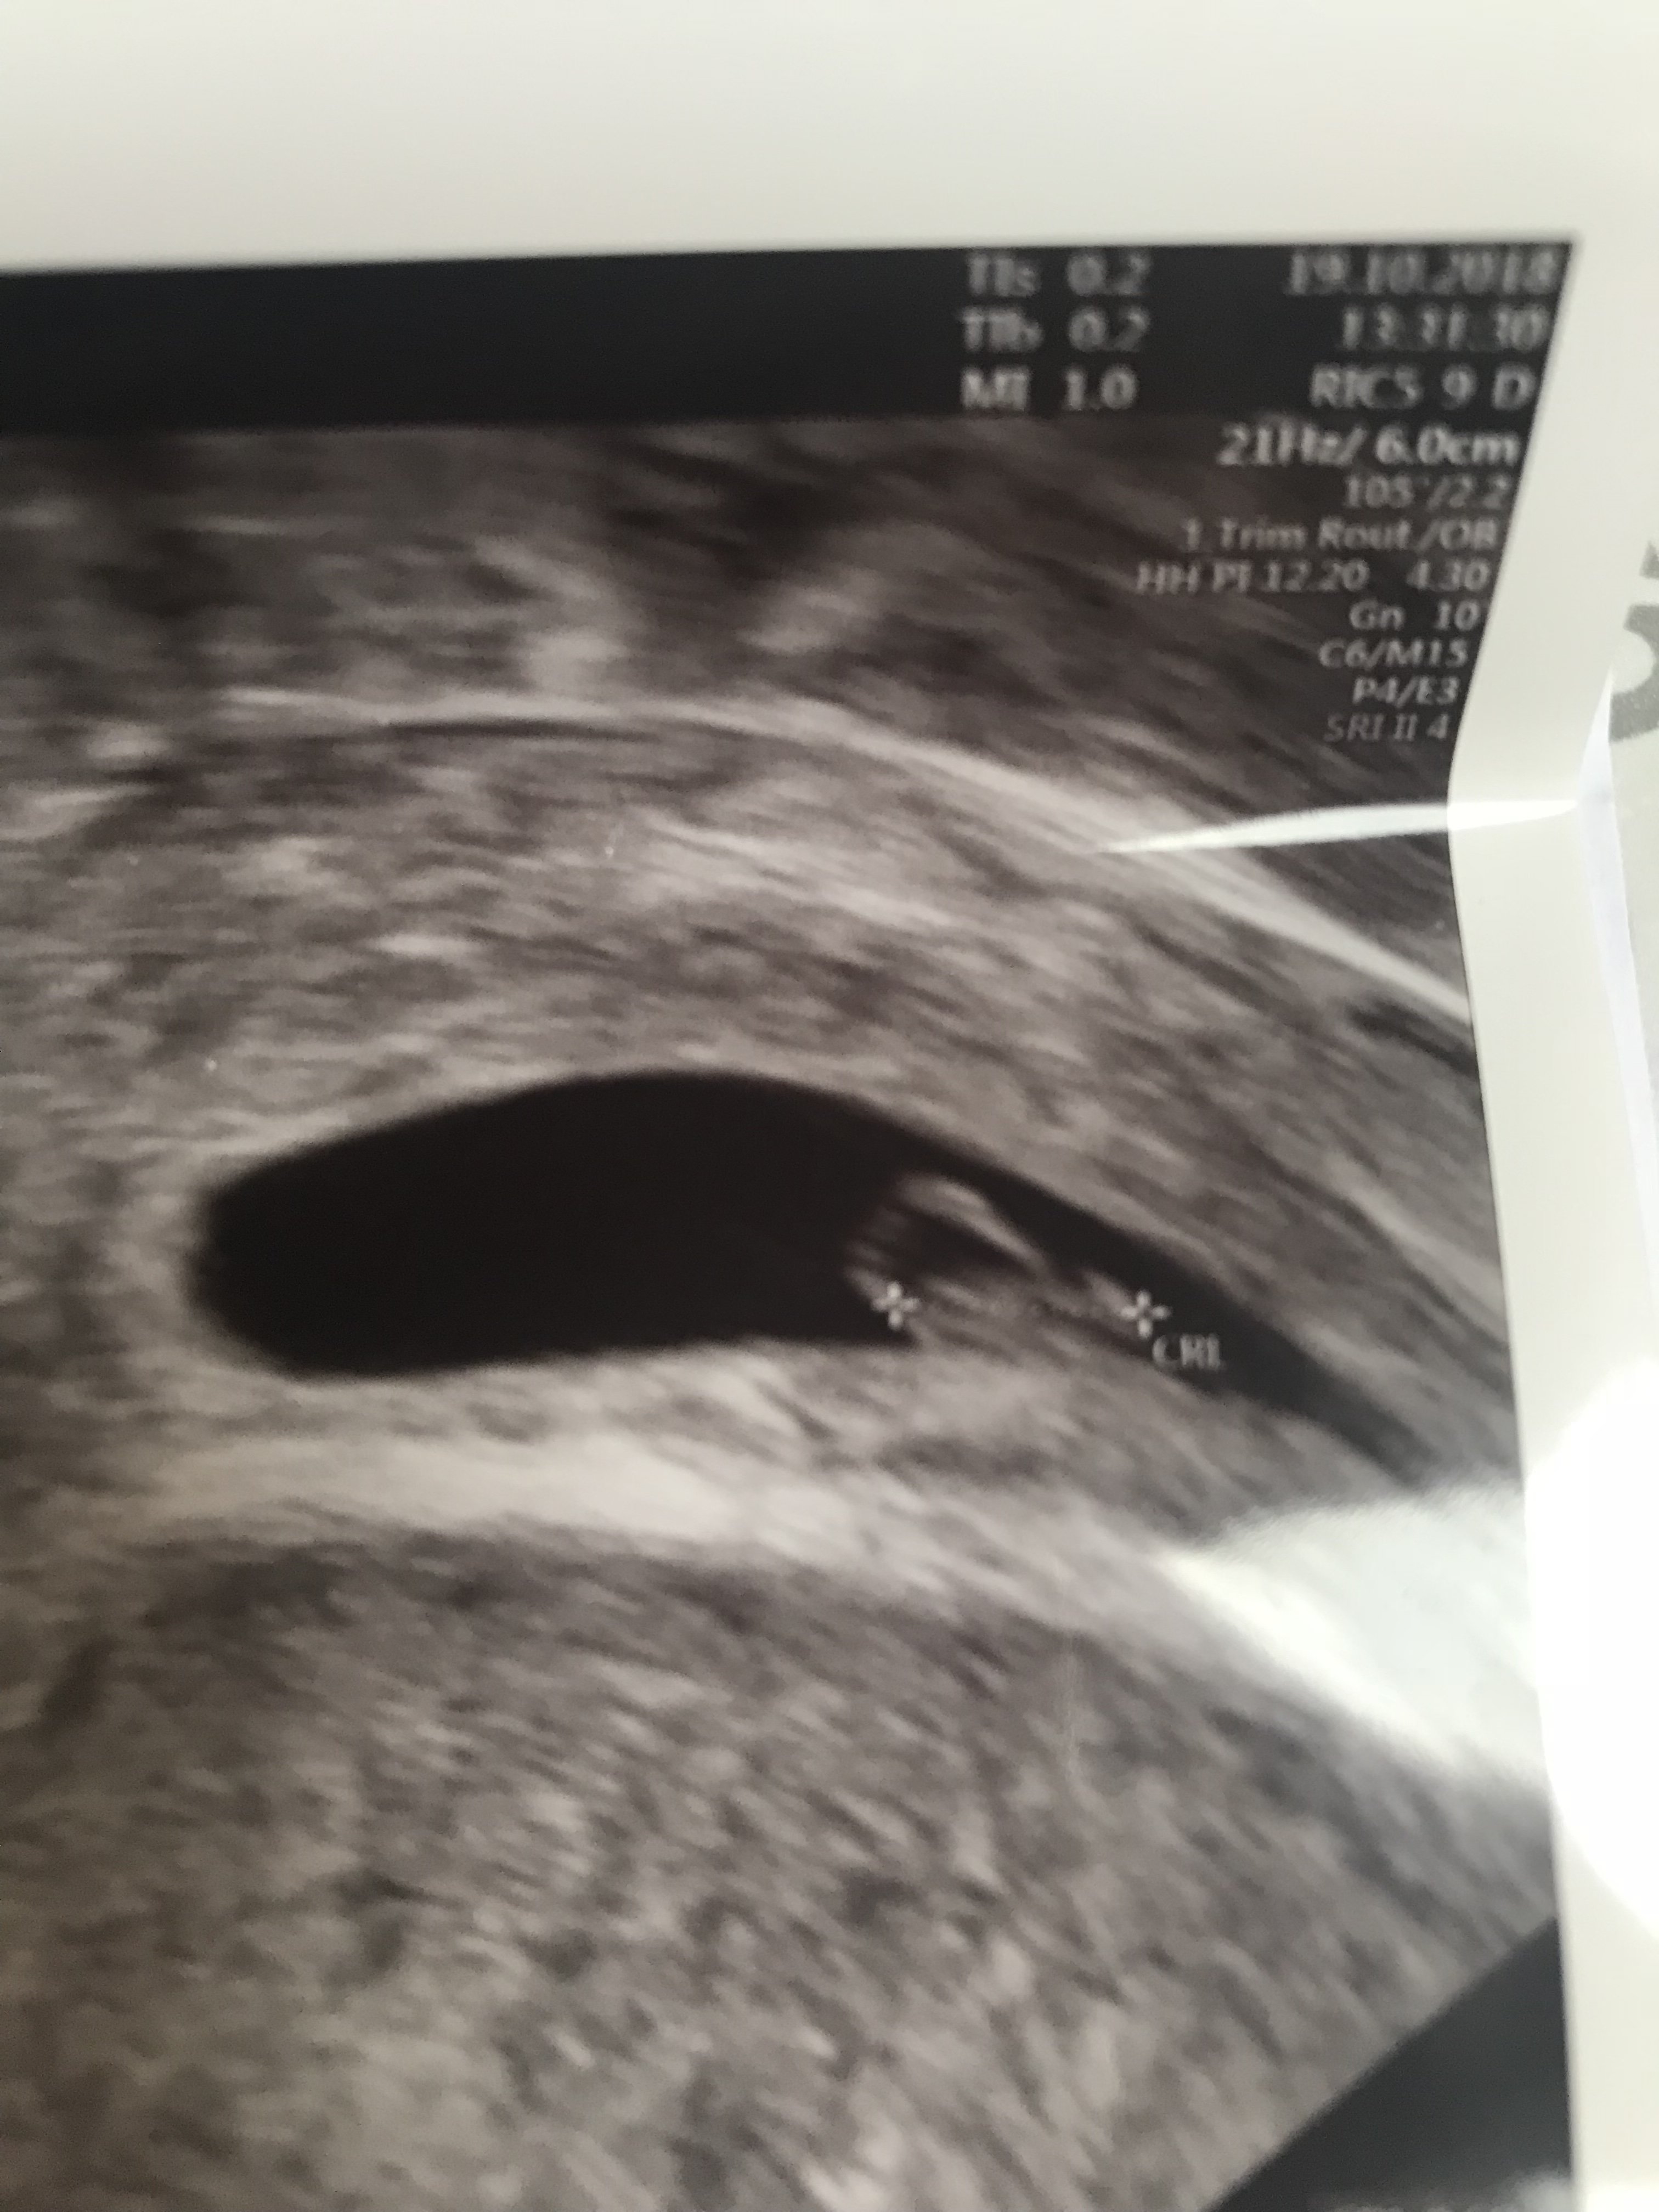

Jestem po wizycie. Wysiedziałam się znowu 5 h na tej poczekalni ale warto było [emoji173] dzidziuś żyje, ma 6 mm. Serduszko bije 120 uderzeń. Nie mogę w to uwierzyć.... :( targają mną takie emocje, ze nie mogę opanować płaczu. Nigdy nie dotrwałam na usg do takiego momentu... zawsze ciąże obumierały szybko a lekarze mnie oszukiwali :( to moje małe szczęście. 6tc3dn

Oby Teraz tylko mój organizm się wyciszył na długie 9 ms... :( a teraz co do plamienia, mam krwiaka ale daleko od dziecka i w niczym nie zagraża i plamie z rany po resekcji przegrody... niestety wiec przy mojej wadzie macicy na plamienia muszę się poki co przygotować.